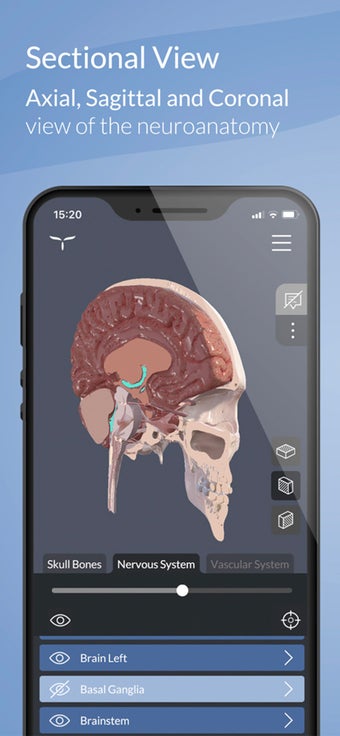

Una aplicación gratuita para Android, de UpSurgeOn.

Esta es una aplicación de aprendizaje gratuita, diseñada para ayudarte a entender el cerebro humano y su anatomía y funciones.

Para ayudar en el aprendizaje y la memorización, la aplicación incluye una vasta colección de textos científicos divididos en tres niveles cognitivos, que van desde una visión general hasta definiciones altamente detalladas.

Además, el módulo "ARTouch" de esta aplicación te permite ver la neuroanatomía de manera híbrida utilizando el modelo físico AnatomyTouch.